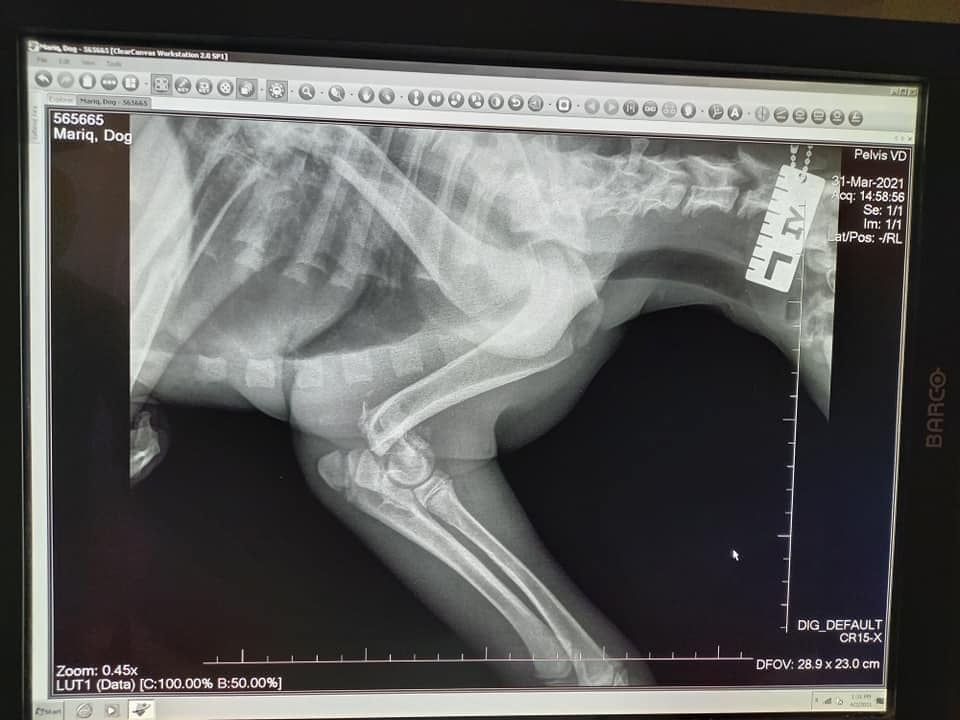

Auch dieser Fall lässt nur erahnen, welche Qualen der Vierbeiner erlitten haben muss: Maria ist ca. 3-4 Monate alt und hatte vier gebrochene Beine. Laut Tierarzt womöglich von mehreren Verkehrsunfällen. Die Kleine muss unglaubliche Schmerzen gehabt haben und konnte nicht mehr laufen. Zum Glück haben Nina & Nuriye Maria gefunden! Laut Tierarzt kann Maria ein normales Leben führen, wenn sie an allen Beinen operiert wird. Dies ist inzwischen für die Hinterläufe und einen Vorderlauf geschehen, morgen wird das letzte Bein operiert. Maria hat die bisherigen OPs gut weggesteckt und wir sind zuversichtlich, dass auch morgen alles gut gehen wird. Die Zuckermaus hat es so verdient, auf allen vier Pfoten das Leben zu erkunden! Aber auch in Bulgarien kosten Operationen etwas und deshalb bitten wir um Unterstützung für Maria.